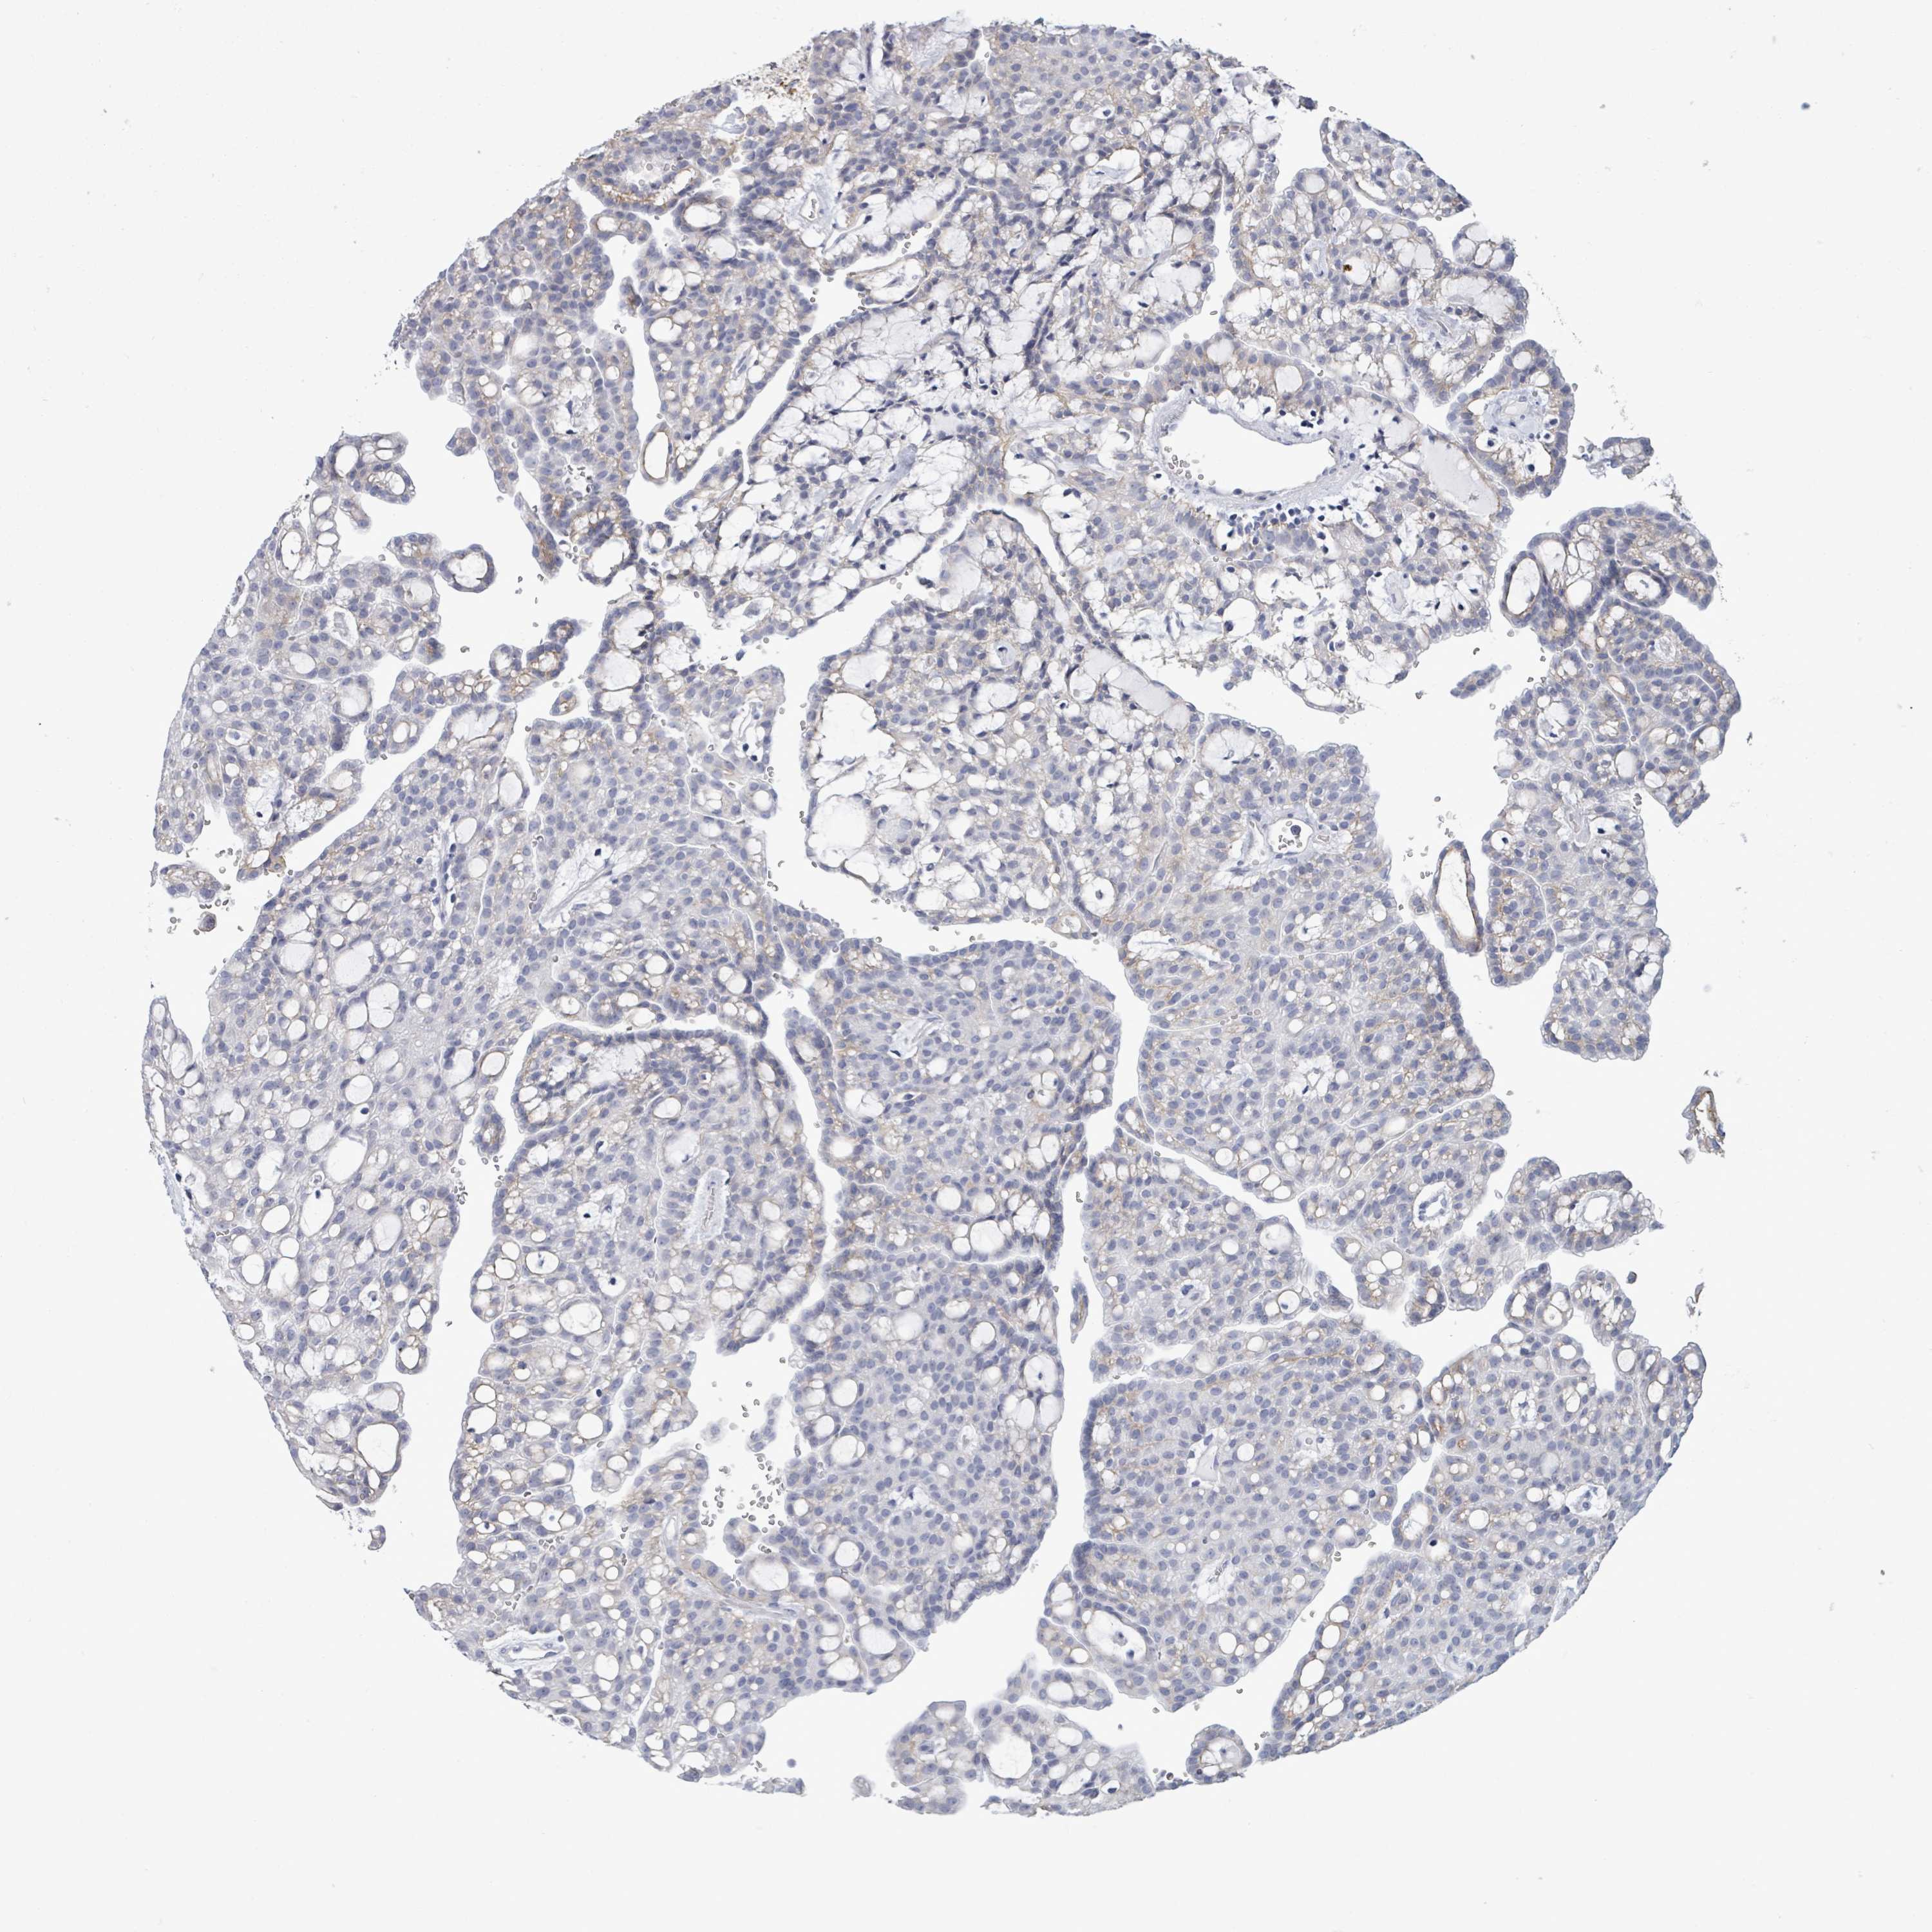

CANCER RENAL CANCER Show tissue menu

KICH TCGA KIRC TCGA KIRC VALIDATION KIRP TCGA PROTEIN RCC CPTAC PROTEIN EXPRESSION

Renal cancer

Kidney renal papillary cell carcinoma